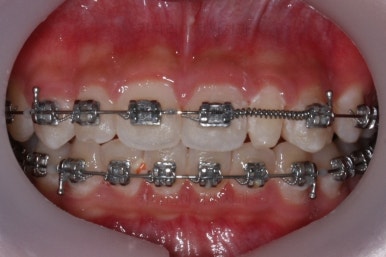

처음 장치를 부착한 이 후 8개월이 흐른 시점이네요. 꽤나 오랫동안 천천히 송곳니를 가지런하게 해줘요.

치료 10개월째의 모습입니다.

이정도면 다 끝난 것 같은 느낌이 드시지 않나요? 과개교합도 개선시켰고 매복치아 덧니도 가지런하게 했어요.

근데 문제는 지금부터였어요.

작은 앞니가 왜소치이다 보니 윗니에는 틈이 남아있고 교합도 조금 엉성한 모습이에요.